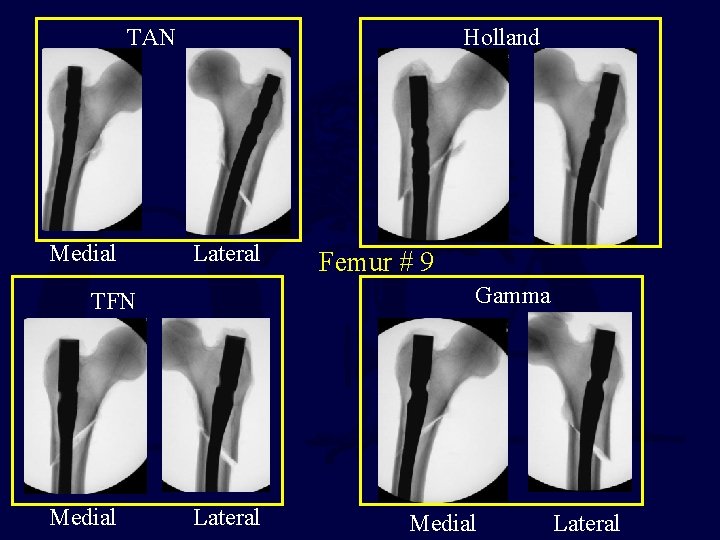

TAN Medial Holland Lateral Gamma TFN Medial Femur # 9 Lateral Medial Lateral

Recommendations The tip of the trochanter or slightly medial is the entry site of choice for antegrade trochanteric nailing of subtrochanteric fractures The lateral starting point, even 2 -3 mms from the tip of the trochanter, is to be avoided Ostrum R, JOT 2005